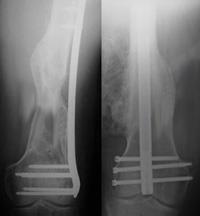

Internal fixation of distal femur fractures

Healed fractures treated with a plate (left) and a rod (right).

If the fracture is in many small pieces above your knee joint, your surgeon will not try to piece the bone back together like a puzzle. Instead, your surgeon will fix a plate or rod at both ends of the fracture without touching the many small pieces. This will keep the overall shape and length of the bone correct while it heals. The individual pieces will then fill in with new bone, called a callous.

When the femur breaks into several pieces, new bone will grow and fill in gaps during the healing process.

In cases where a fracture may be slow to heal, such as when a patient is elderly with poor bone quality, a bone graft may be used to help the callous develop. Bone grafts may be taken from the patient (most often from the pelvis) or from a tissue bank (cadaver bone). Other options include the use of artificial bone fillers.